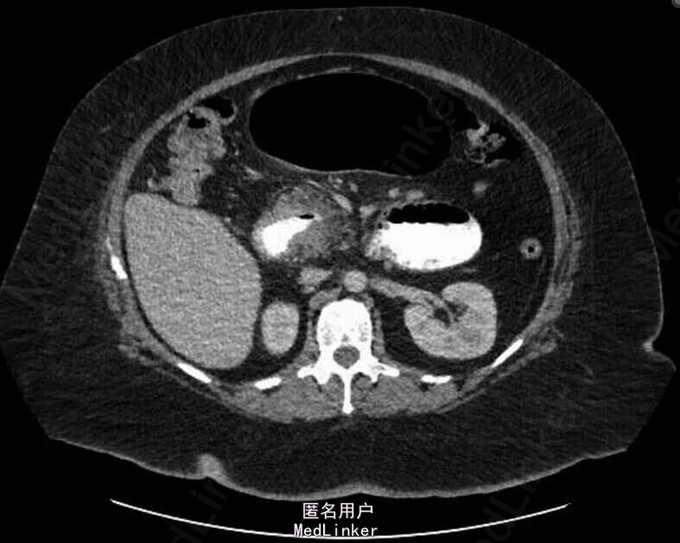

查体:发热(患者诉进行性加重,具体不详),心动过速,腹部稍膨隆。辅助检查:实验室检查提示白细胞增高(22×109/),CRP(359 mg/dl),腹平片提示胃十二指肠以及近段空肠扩张。CT检查提示胃束带移位,近段空肠梗阻,胃部出现扩张。

诊断:急性肠梗阻处理:迅速予以补液以及使用广谱抗生素。情况稳定后予以行腹腔镜下探查,证实胃束带确实有移位,而且近段的空肠出现了急性小肠梗阻,予以摘除胃束带。